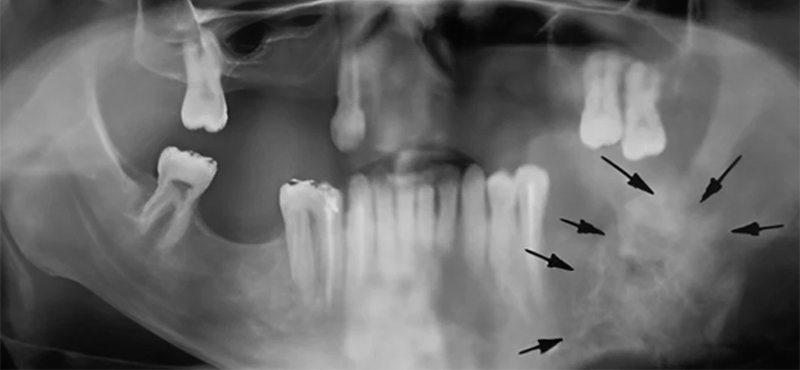

• Radio panoramique : bilan bucco dentaire et osseux.

• Scanner : appréciation des atteintes des structures osseuses.